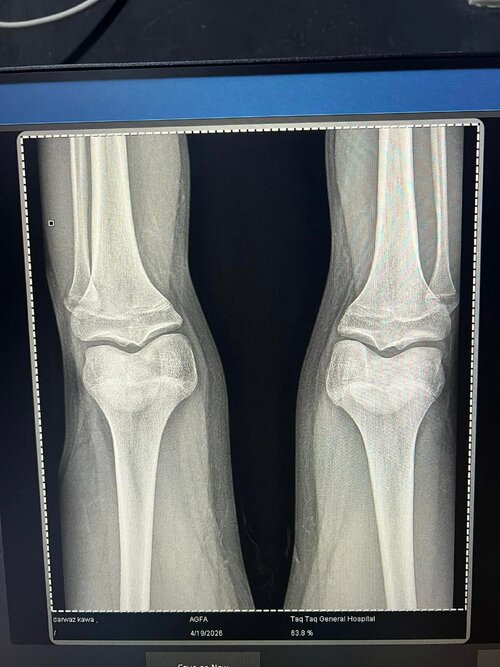

So. Igot diagnosed too late that im ghd and my plates are fusing and doc prescribed 6 ius daily and he said i wouldve prescribed u ai if u came at 14 :feelsrope::feelsrope:

Ai def cope at this point youd have to hop on other stuff depending how much time you got which i dont know because i cant figure that out